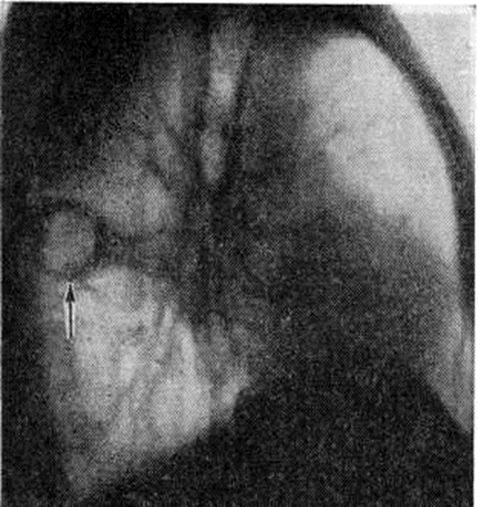

В диагностике основную роль играют рентгенологические методы исследования. Рентгенологические картина первичного комплекса характеризуется, четырьмя признаками: появлением, чаще во 2—5-м сегментах лёгких, крупного очага или участка уплотнения лёгочной ткани средней интенсивности, однородной структуры с чёткими очертаниями, расположенного кортикально (очаг первичной пневмонии); расширением и уплотнением за счёт увеличения регионарных лимфатических, узлов корня лёгкого на этой же стороне; наличием связующей дорожки между очагом в лёгком и корнем лёгкого, обусловленной инфильтрацией лёгочной ткани вокруг сосудов и бронхов; уплотнением плевры или появлением плевропульмонального тяжа на уровне лёгочного очага (рисунок 2). В фазе рассасывания на месте первичного аффекта формируются очаги, которые уплотняются и кальцинируются, образуя небольшой одиночный кальцинированный очаг (очаг Гона) или несколько крошковидных кальцинатов; в регионарных лимфатических, узлах также образуются кальцинаты — формируется картина кальцинированного первичного комплекса. На месте первичного аффекта могут образоваться крупные, чётко очерченные, с выраженным кальцинозом (смотри полный свод знаний) участки уплотнения — первичные туберкулемы. Редко при прогрессировании процесса наблюдается возникновение каверн (смотри полный свод знаний: Каверна), иногда развиваются ателектаз, плеврит.

Рис. 2.

Рентгенограмма грудной клетки при первичном туберкулёзном комплексе (прямая проекция): 1 — участок уплотнения лёгочной ткани (очаг первичной пневмонии); 2 — инфильтрация периваскулярной и перибронхиальной ткани между очагом в лёгком и корнем лёгкого (дорожка); 3 — расширенный и уплотнённый корень правого лёгкого.